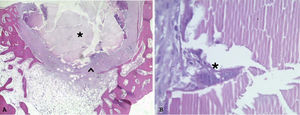

En cuanto a los restos de biomaterial, en las muestras del centro de la zona quirúrgica fueron visibles en 5 muestras caso, con una media de un 16% respecto al total del corte (fig. 5). En las muestras de la periferia, fueron visibles en 2 de los 11 conejos que completaron el estudio, ambas con un 10% de biomaterial remanente respecto al total de corte.

En todas las muestras caso hubo presencia de células inflamatorias agrupadas: en 5 de ellos, tanto en las muestras del centro como en la muestra de la periferia, en 3 solo en el centro y en 3 solo en la periferia, siendo la diferencia significativa entre las muestras casos y controles p <0,05. En todas ellas el porcentaje de células inflamatorias fue entre un 5 y un 10% respecto al total de células observadas (fig. 5A). Solo en una de las patas control fueron visibles células inflamatorias agrupadas, en la muestra del centro.

Similar a las células inflamatorias, en todas las muestras caso hubo aumento de la presencia de células precursoras óseas (entre un 5 y un 10% de osteoblastos y osteocitos) respecto a las muestras control, con significación p <0,05. Siendo similar en las muestras del centro y en las de la periferia (fig. 5B). Solo en una de las patas control se visualizó un aumento de osteoblastos y osteocitos, en la muestra del centro.

En cuanto al estudio histológico, el cierre de la circunferencia cortical fue prácticamente completo en todas las patas caso y el porcentaje de células inflamatorias de los casos fue relativamente bajo, por lo que a las 10 semanas tras la cirugía no parece haber una gran respuesta inflamatoria, si bien fue algo superior a las patas control, esperable dado el tiempo de evolución; además, la presencia de este tipo de células fue principalmente en la zona donde faltaba hueso por formarse o alrededor de los restos de biomaterial (fig. 5A). Algo similar ocurre con las células precursoras óseas, que aparecieron principalmente alrededor de la zona de defecto de cierre de la cortical (fig. 5B).